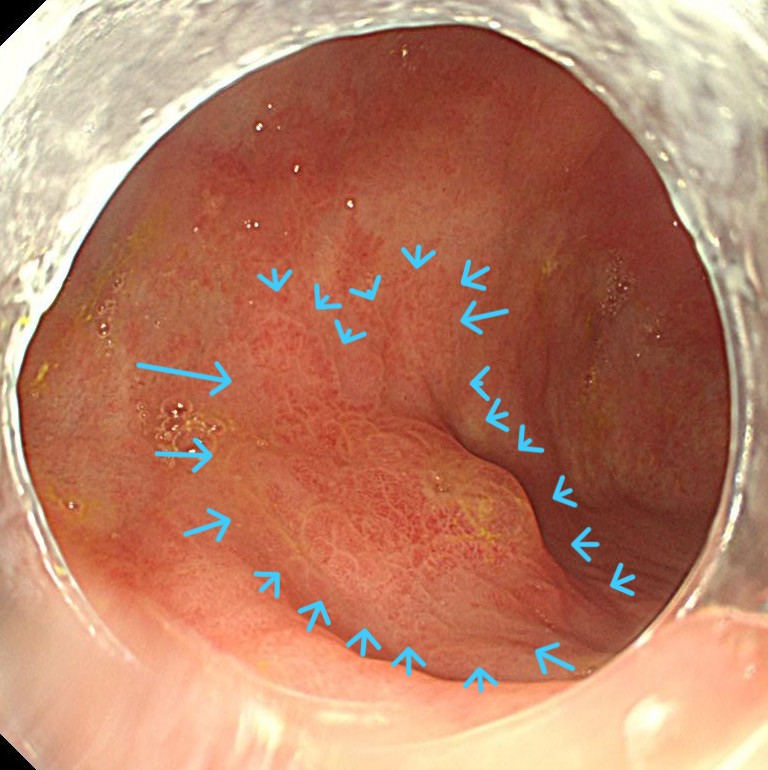

前庭部に中心陥凹、周囲発赤するIIA+IICがん部を認めます。